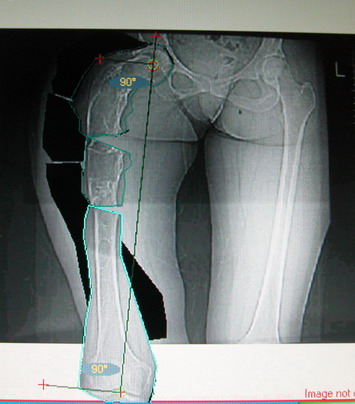

На мой взгляд, для того, чтобы правильно исправить данную деформацию, необходимо обследование больного, которое должно включить в себя, помимо осмотра: 1. Рентгенограммы ( передне-задние и боковые)нижних конечностей на всю длину стоя . 2. Компьютерная томография для измерения длины нижних конечностей. 3. Комьютерная томография тазобедоенных, коленных и голеностопных суставов для измерения углов антеверсии тазобедренных суставов и ротации голеней. Это тот минимум, который должен входить в предоперационное обследование каждого больного с тяжёлыми формами деформаций конечностей.

Поскольку в данном случае имеется дело с довольно большой деформацией с укорочением, одномоментная её устранение с внутренней фиксацией, чревато с одной стороны неправильной коррекцией, с другой, нейроваскулярными осложнениями.

Моё мнение, что двойная остеотомия бедра с аппаратом Илизарова + Гексаподный механизм, или Тэйлора, В данной ситуации является методом выбора. Я очень извеняюсь за качество прилагаемых снимков, в которых я постарался отразить разницу междe одной и двумя остеотомиями бедра.